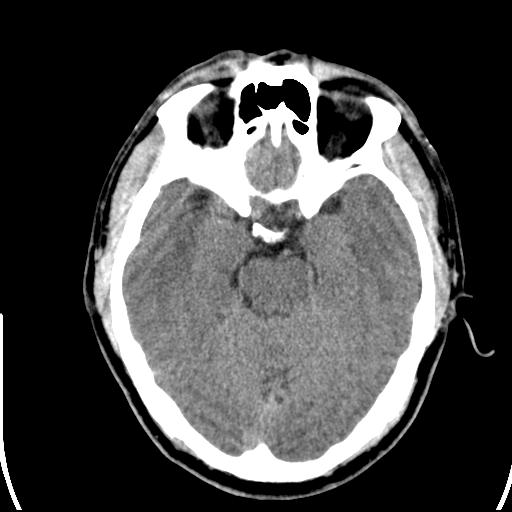

头皮下高密度结节影???临床上在老年男性比较常见。大家看看是什么?成因是? 本例患者,男性,51岁。外伤来诊。无染发史及发根植入史。

考虑异物。

皮下钙化点

没见过,可能为毛囊钙化。

考虑钙化。